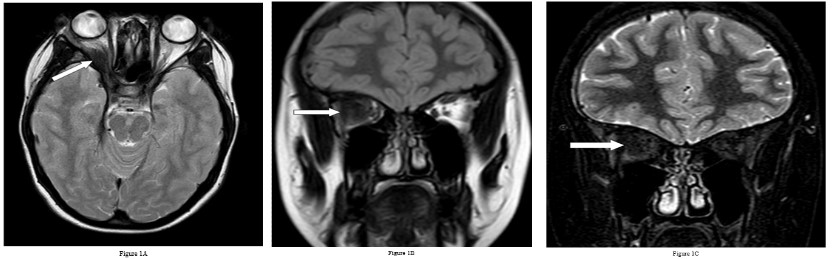

She underwent Magnetic Resonance Imaging (MRI) of her brain that identified a soft tissue lesion within the right orbit involving the posterolateral aspect and exhibited low signal on T1, T2, Fluid Attenuated Inversion Recovery (FLAIR), Short Tau Inversion Recovery (STIR) sequences, and uniform gadolinium contrast enhancement (Figures 1,2). There was no evidence of diffusion restriction. The orbital lesion was exerting mass effect on the adjacent optic nerve and displacing the adjacent extraocular muscles. The pituitary gland was enlarged on the sagittal T1-weighted sequence with loss of the normal T1 high intensity of the posterior pituitary gland. The pituitary stalk was enlarged and enhanced with gadolinium contrast, as did the pituitary gland. There was abnormal dural thickening and contrast enhancement involving the skull base from the posterior clinoid process to the clivus.

Figure 1: Demonstrating axial T2 (A) coronal T2 FLAIR (B) and coronal STIR (C) images of both orbits. Mass lesion seen in the right orbit with a low signal on T2, T2 FLAIR and STIR sequences (solid arrows), which is difficult to distinguish from the extraocular muscle. It medially displaces the optic nerve. Mild proptosis of the right orbit is seen